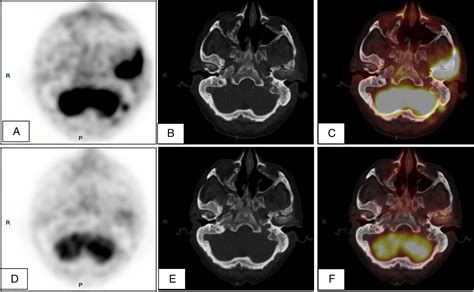

Diagnosis requires a high index of clinical suspicion. An ENT specialist will typically perform an otoscopic examination to identify the characteristic granulation tissue. To confirm the diagnosis and determine the extent of the bone involvement, imaging is mandatory.

CT Scan Excellent for identifying bony erosion and the extent of osteomyelitis.

MRI Superior for assessing soft tissue involvement and intracranial spread.

Technetium-99 Bone Scan Highly sensitive for detecting active bone inflammation early.